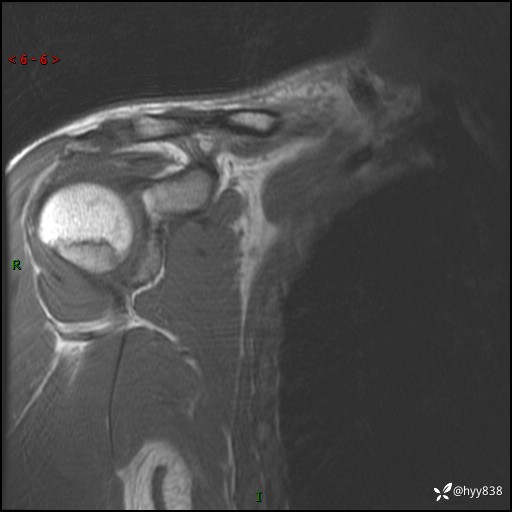

MRI(cor T1WI+T2WIfs+axi T2WIfs)